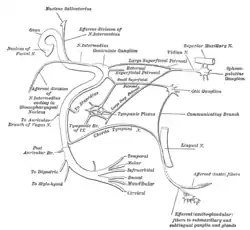

The course of the facial nerve is shown here | |

Mandibular division of the trifacial nerve. Plan of the facial and intermediate nerves and their communication with other nerves.

Plan of the facial and intermediate nerves and their communication with other nerves. The course and connections of the facial nerve in the temporal bone.